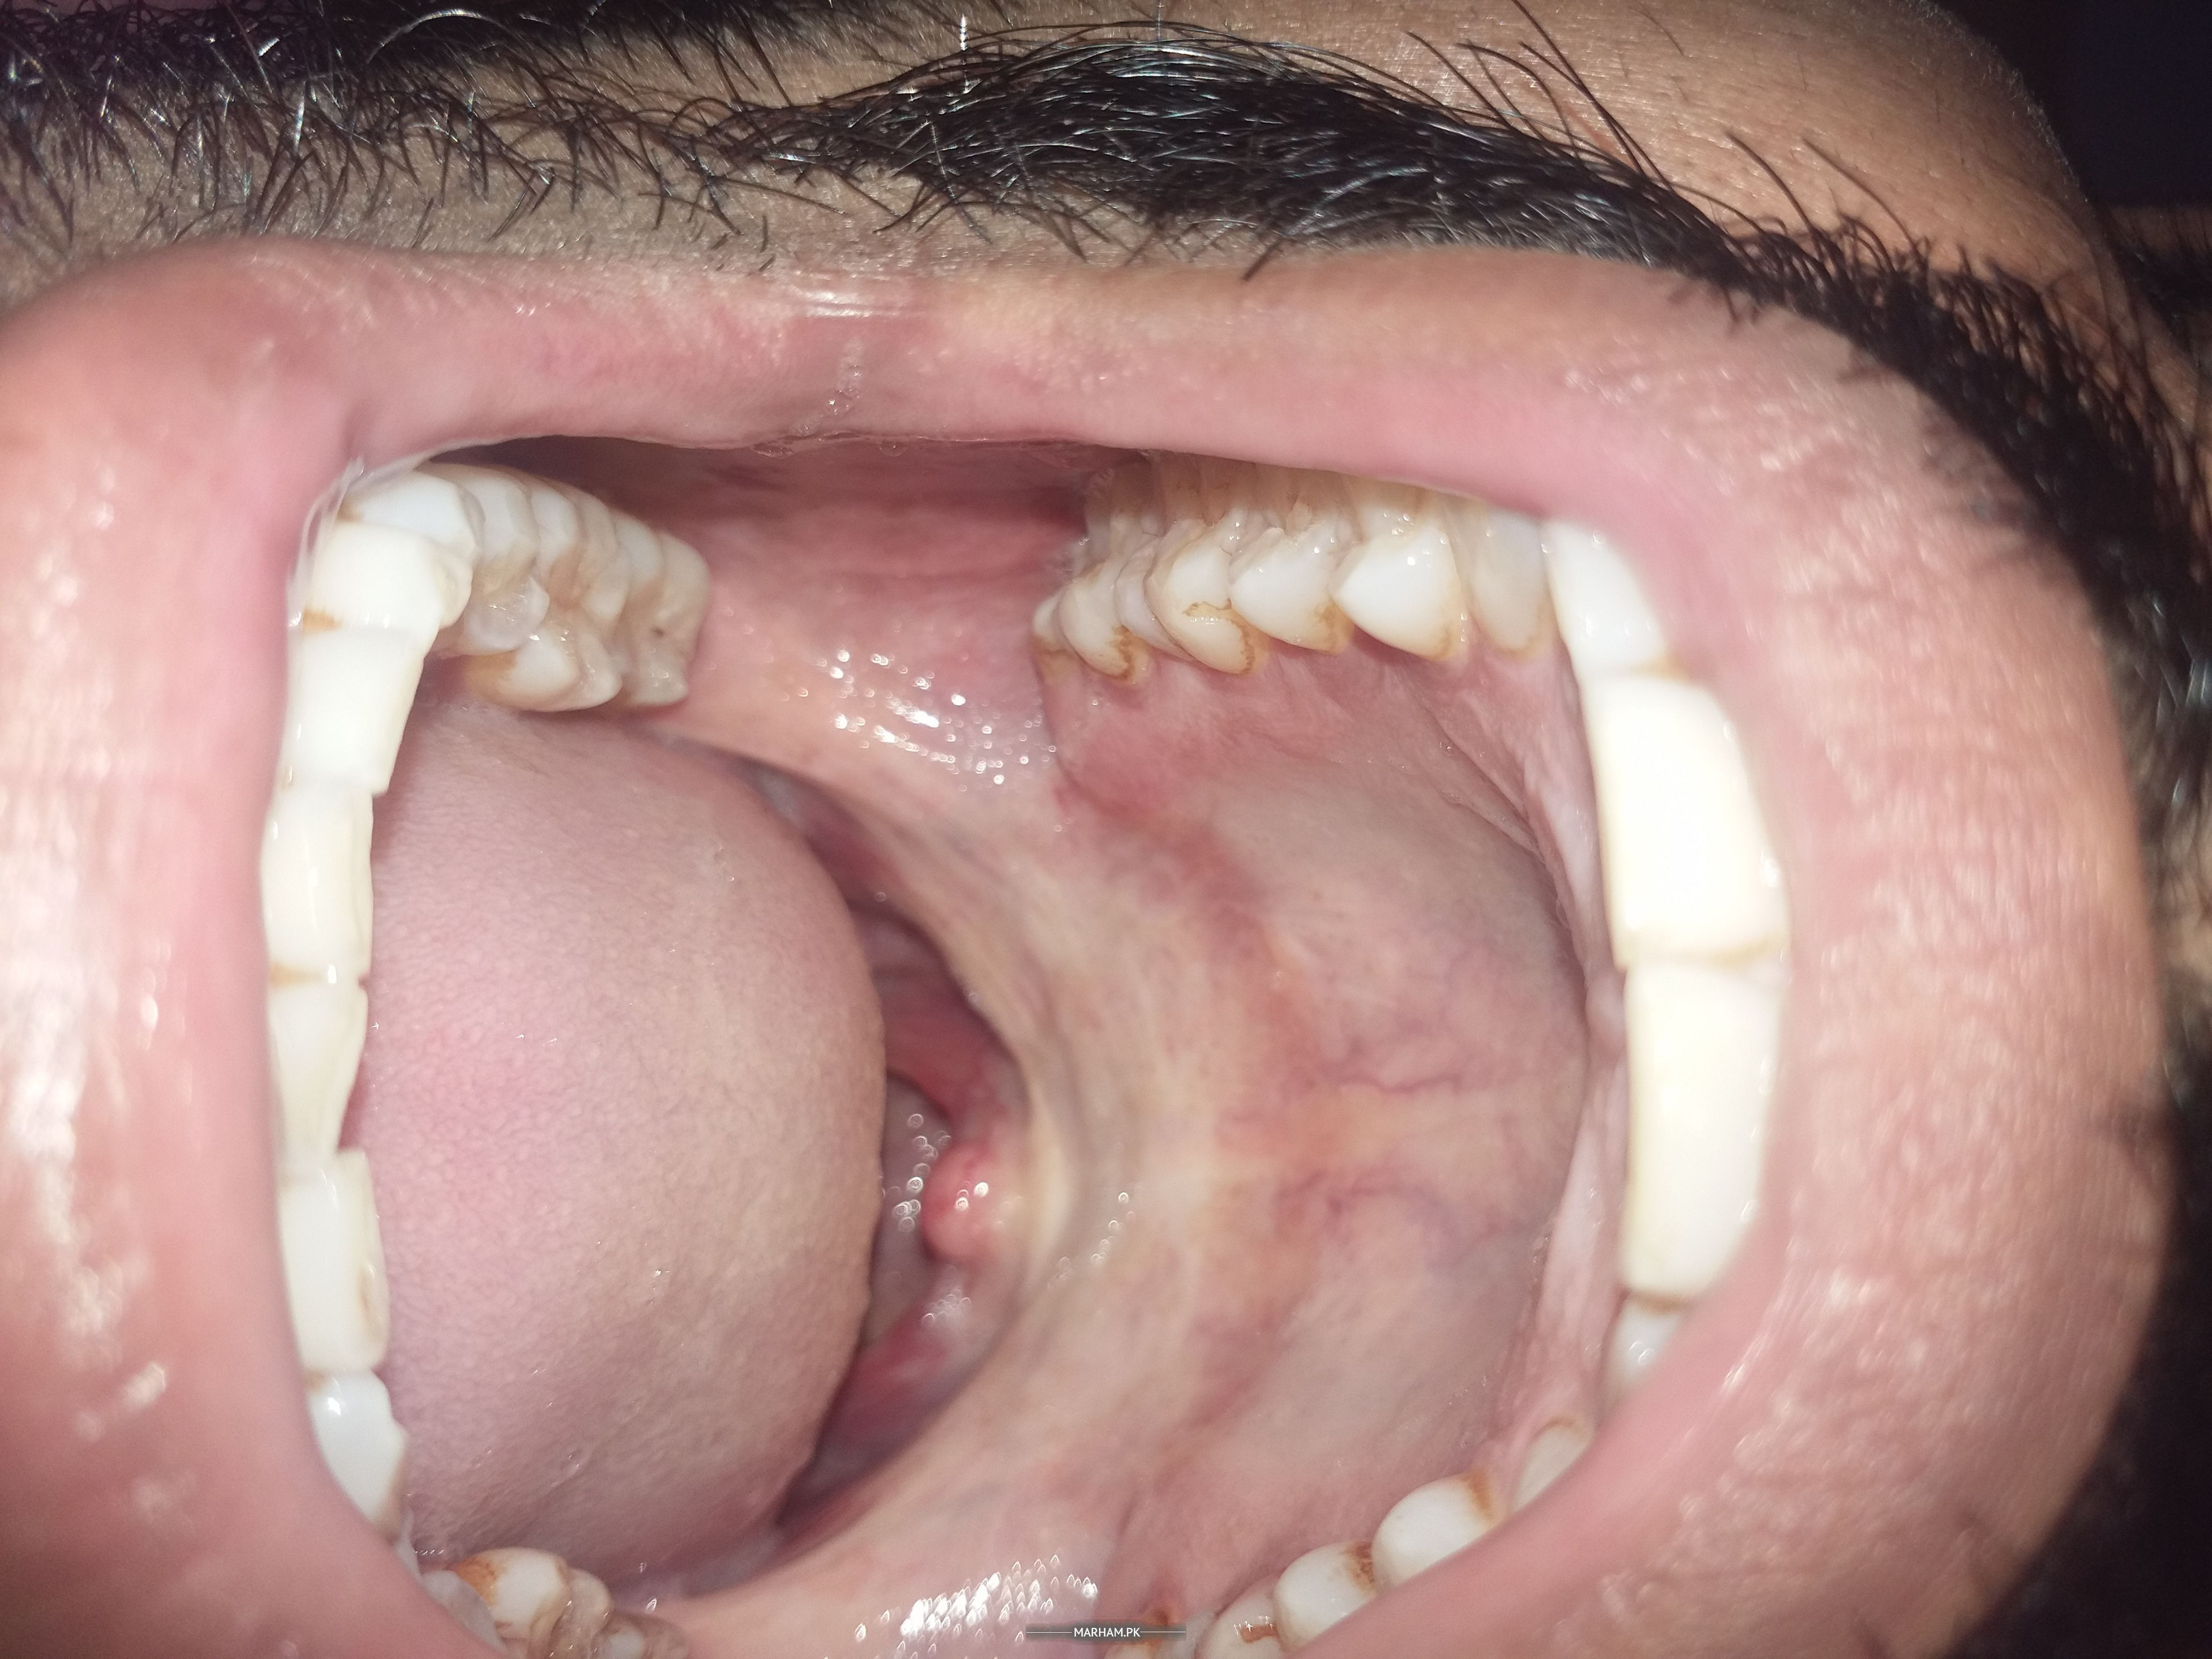

Asking for Self, Male, 26 years old, Karachi

I can put 3 fingers in my mouth. I have some zakham at my inside jaws. There is whiteness in my mouth. I visited to BDS he said i am suffering from submucous Fibrosis. Now i have stop eaten areca and betal nut. I sm taking sangobian and Vidaylin T tablet daily. After lefting these, the disease is still progressive or it may stop?. Also i want a right doctor for this disease kindly guide me where to visit in Karachi?

can u please share picture of inside of your mouth?

Pic 2